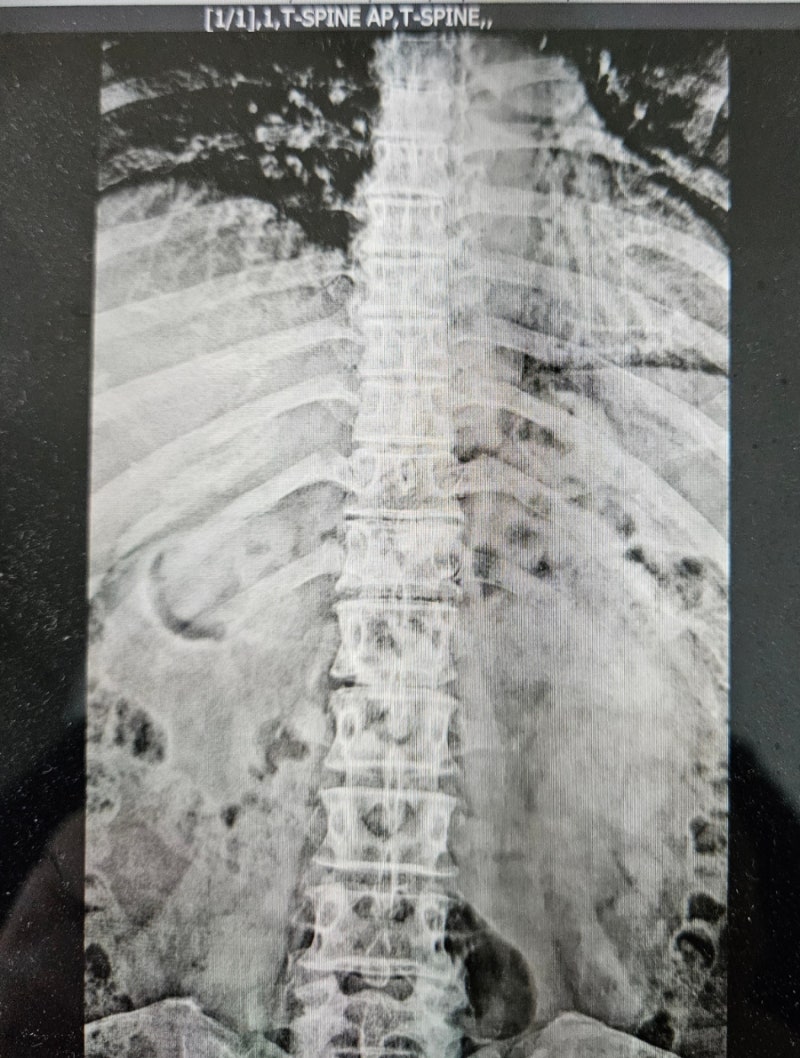

촬영부위: 흉추 (Thoracic Spine)

촬영방향: AP 및 LAT (정면 및 측면)

흉추 12번(T12) 압박골절 확인됨

척추체 전방의 함몰, 쐐기형 변형(wedge deformity) 관찰해당 부위 국소 후만 변형 유발

56세 여성 환자의 흉추 12번 부위 압박골절에 따른 구조적 변형이 영상에서 확인됩니다. Cobb angle(T11–L1)은 약 28도이며, 이는 정상 상한선(15도)을 초과하고, 사고 전 정렬이 정상(0~10도)이었다면 최소 15도 이상의 후만각 증가로 판단됩니다.